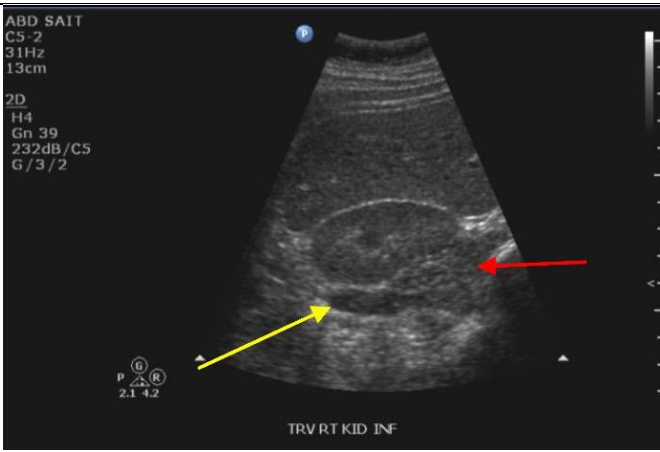

7

Q

Label the Red and blue arrows

A

Red: Right quadratus laborum

Blue: Right kidney pyramid of the medulla